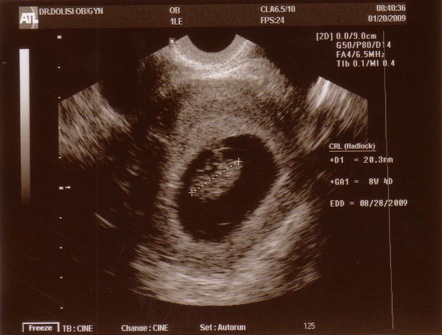

Yeay! We saw a heartbeat!

We are back from our first official OB appointment with Dr. Dolisi. He is very sweet, DH and I really liked him. He did an internal sonogram and we saw the baby's little heartbeat. Our little baby is measuring at 8.5 weeks old. We are so excited! Image Attachment(s):